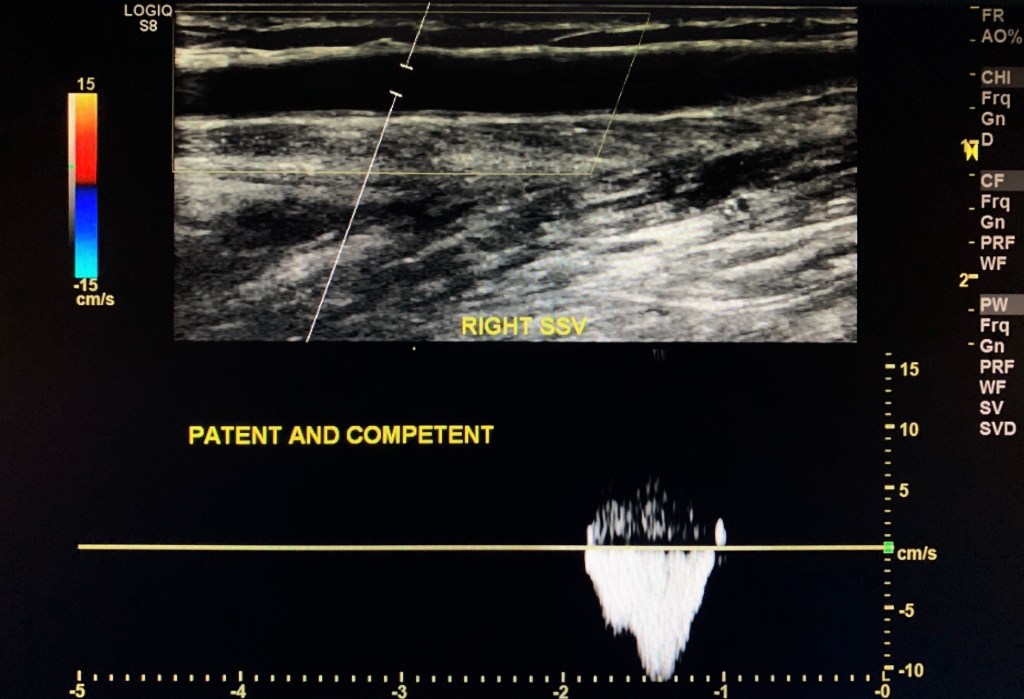

Small Saphenous Vein

The Small Saphenous Vein (SSV) did not elicit an incompetent response to distal augmentation.

SSV was patent and competent.